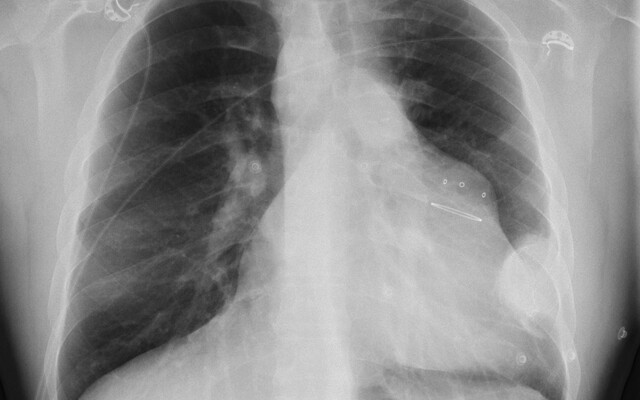

Zie jij wat er aan de hand is? Bij de beeldquiz stel je een diagnose aan de hand van een foto en een korte casus. Alle beeldquizzen Recent toegevoegd Beeldquiz Sproetjes, café-au-laitvlekken en cutane noduli Beeldquiz Pijnlijke handen en gezwollen vingers Beeldquiz Bloedarmoede en nagelafwijkingen Beeldquiz Onsamenhangende spraak Moeilijkste Beeldquiz Een man met een 'uitpuiling van den borstwand' Beeldquiz Een vrouw met pijn in de achtervoet Beeldquiz Een meisje met een tumor op de borst Beeldquiz Een man met een pijnlijke, gezwollen enkel Meest gemaakt Beeldquiz Een vrouw met een paarsrode neus Beeldquiz Een peuter met loslatende nageltjes Beeldquiz Zwelling in de buik na een hoestbui Beeldquiz Een 54-jarige man met toenemende buikpijn